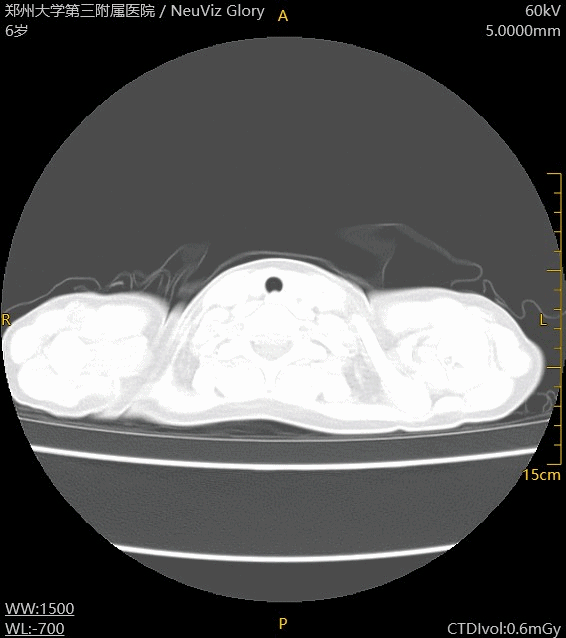

6岁儿童,发热2小时

CT胸部平扫:左肺下叶外基底段胸膜下可见结节状高密度影,边界清晰,左肺

上叶胸膜下少许条索影

诊断:左肺下叶胸膜下结节,左侧胸膜少许间质改变

扫描参数:

60kV,自动mAs

CTDIvol:0.6mGy

DLP: 12.0mGy*cm

ED: 0.204mSv(k=0.017)